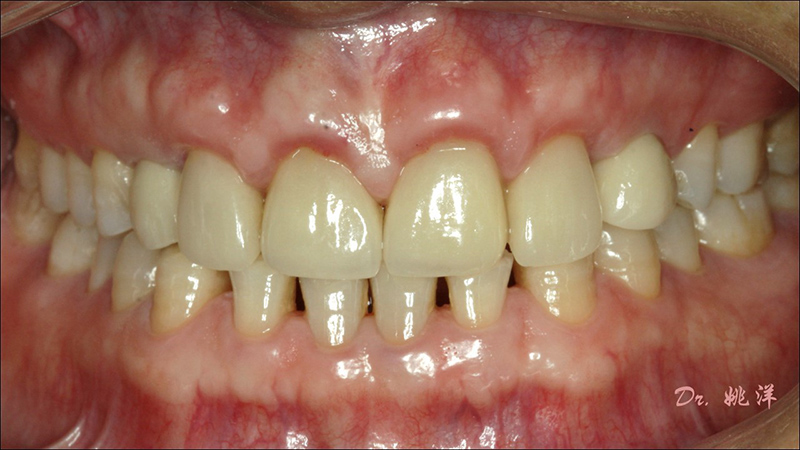

從最終修復(fù)效果可以看出:23,24間隙不足修復(fù)兩顆,修復(fù)為1顆牙。因?yàn)榻?jīng)過(guò)數(shù)字化設(shè)計(jì)和精確導(dǎo)航植入,修復(fù)體齦緣協(xié)調(diào)自然

術(shù)后照片

恢復(fù)了正常的淺覆合淺覆蓋